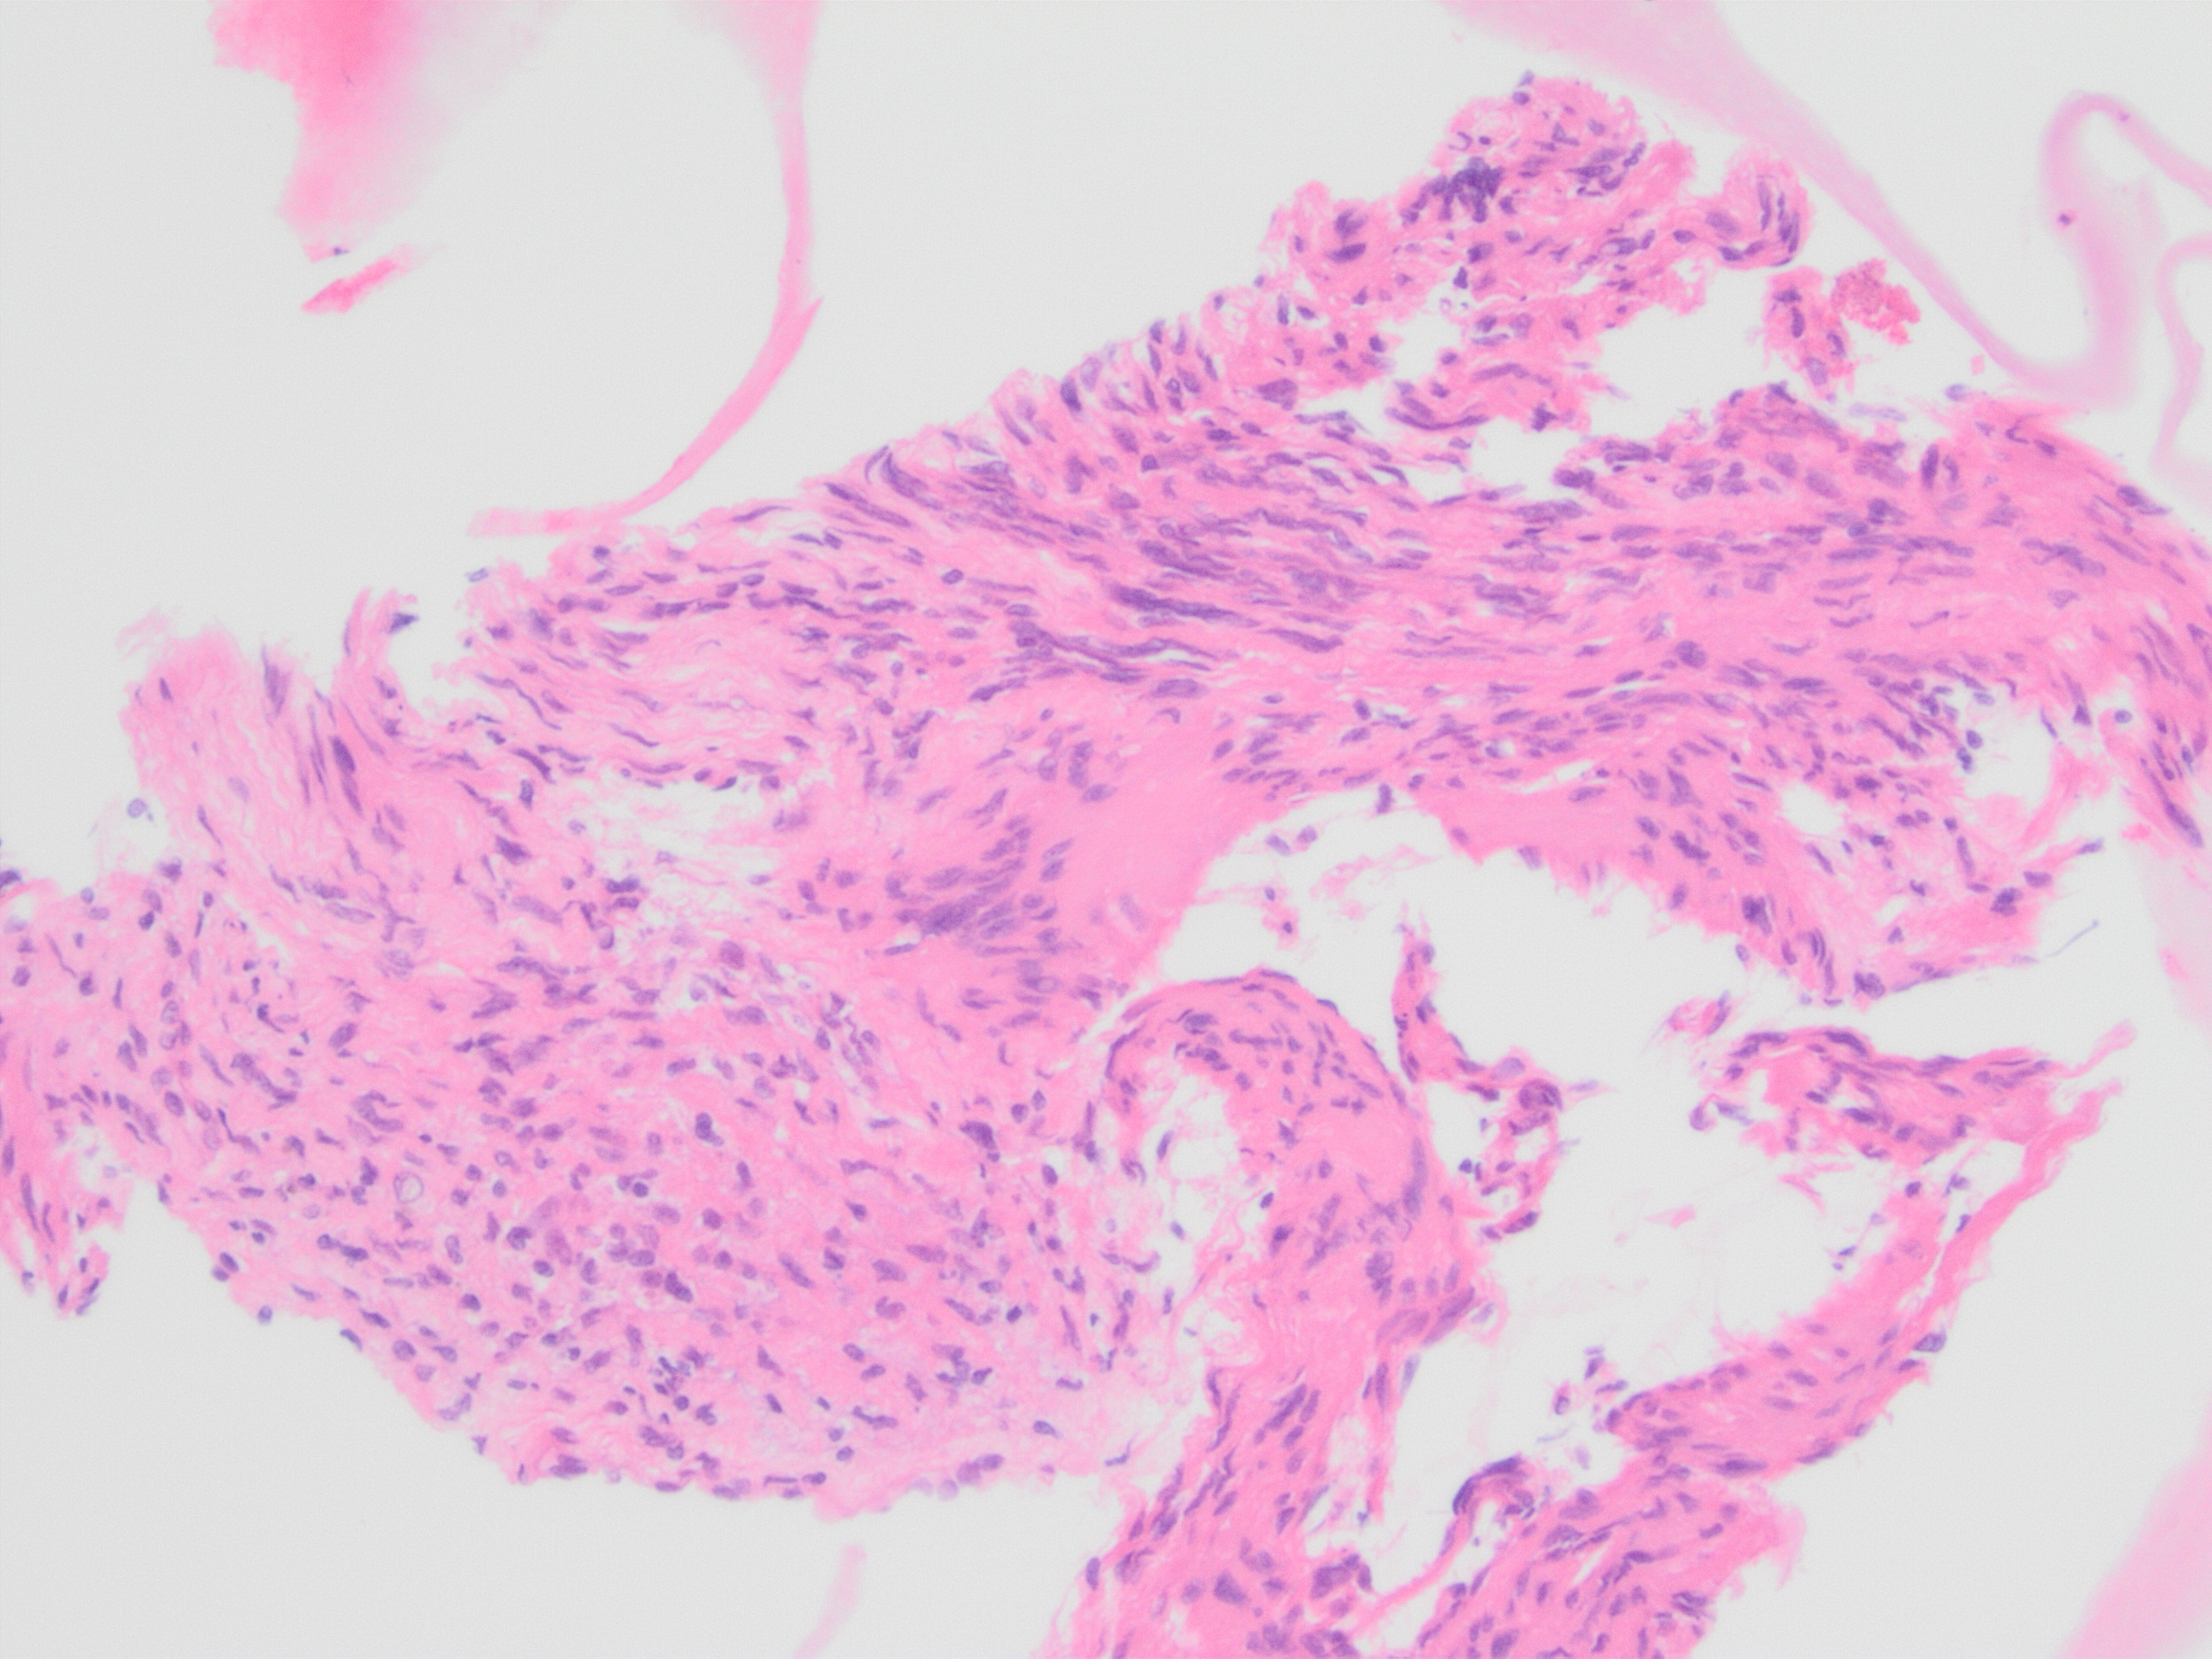

Immunohistochemistry was diffusely positive for Sox-10 and negative for C117 (C-kit), DOG1, SMA, CD34, supporting neural crest origin. On cytology, note a large tissue fragment with variable cellularity showing oval to wavy, “fishhook” nuclei on higher magnification and indistinct cell borders. On cell block, note the abundant filamentous cytoplasm and subtle nuclear palisading.